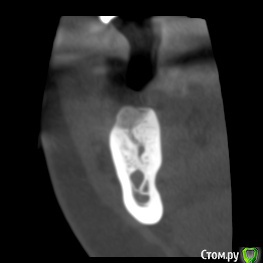

dentikl Опубликовано 26 ноября, 2019 Поделиться Опубликовано 26 ноября, 2019 В августе планировали имплантацию отсутсвующего 46 .Сделали кт,почистили .3 месяца. Ждать или уже ставить? Ссылка на комментарий

dentikl Опубликовано 26 ноября, 2019 Автор Поделиться Опубликовано 26 ноября, 2019 +1 ставитьто,что на первом скане -это коллатерали которые усложняют прогноз? Ссылка на комментарий

red_butler Опубликовано 26 ноября, 2019 Поделиться Опубликовано 26 ноября, 2019 то,что на первом скане -это коллатерали которые усложняют прогноз?Похоже 1 Ссылка на комментарий